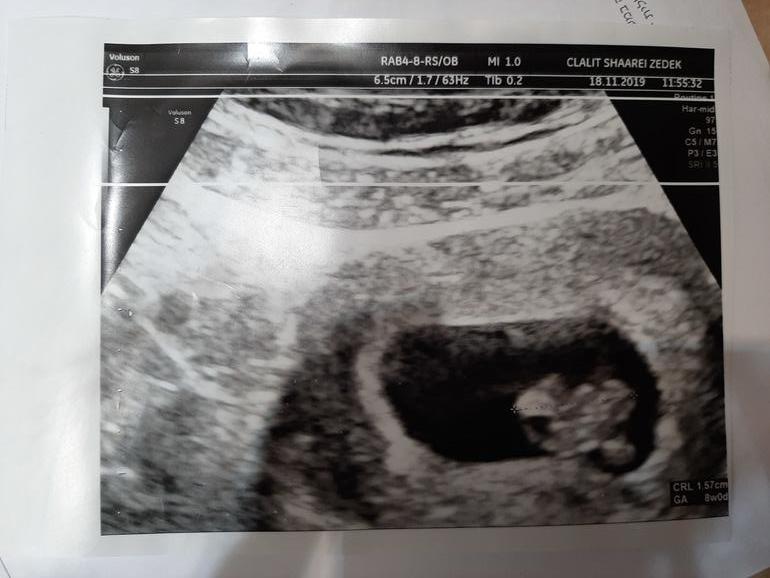

Увидели свою кроху, показали сердечко) Врач пошутил, что у нас девочка, потому что ооочень красиво все на узи))

По размерам 16мм. А у нас только 7 недель и 4 дня было.